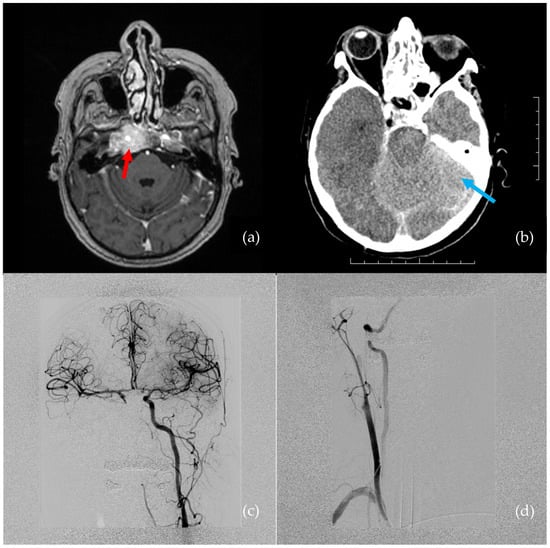

A 66-year-old female presented with hypesthesia and pain in the right half of the face. A tumor was suspected. She had a history of metastatic mammary ductal carcinoma, which was treated 5 years prior to the visit. Magnetic resonance imaging (MRI) showed a right cavernous sinus tumor, which extended to the cavum Meckeli and encircled the right ICA cavernous segment (Figure 1a). A transsphenoidal endoscopic biopsy was performed for a pathological workup.

The estimated blood loss was 1.5–2 L in 5 min. Crystalloids and red blood cell transfusions were administered by the anesthesiology team. Despite these measures, the patient was in critical condition. Digital subtraction angiography (DSA) revealed a right ICA occlusion, though there was good collateral flow through the anterior and posterior communicating arteries (Figure 1c,d). Throughout the DSA examination, the patient was hemodynamically unstable, with bradycardia progressing to asystole. Extensive cardiopulmonary resuscitation (CPR) was performed for approximately 4–5 min. Due to the right ICA occlusion and good collateral flow through the anterior communicating artery, no endovascular intervention was indicated.

A subsequent brain CT was performed immediately after the DSA. The CT revealed a small subarachnoidal hematoma adjacent to the right cavernous sinus, and, overall, both the white and gray matter had dedifferentiated as a result of prolonged hypotension and CPR (Figure 1b).

Figure 1. Pre- and postoperative images show iatrogenic injury to the internal carotid artery (ICA). (a) Preoperative MRI: tumor involving the right cavernous sinus, encircling the ICA (indicated by red arrow). (b) Postoperative brain CT: ischemia and edema in the right hemisphere (indicated by blue arrow). (c) Selective left ICA angiogram: good collateral flow through the anterior communicating artery to the right anterior cerebral artery and middle cerebral artery territory. (d) Selective right ICA angiogram: occlusion of the cavernous segment of the right ICA.